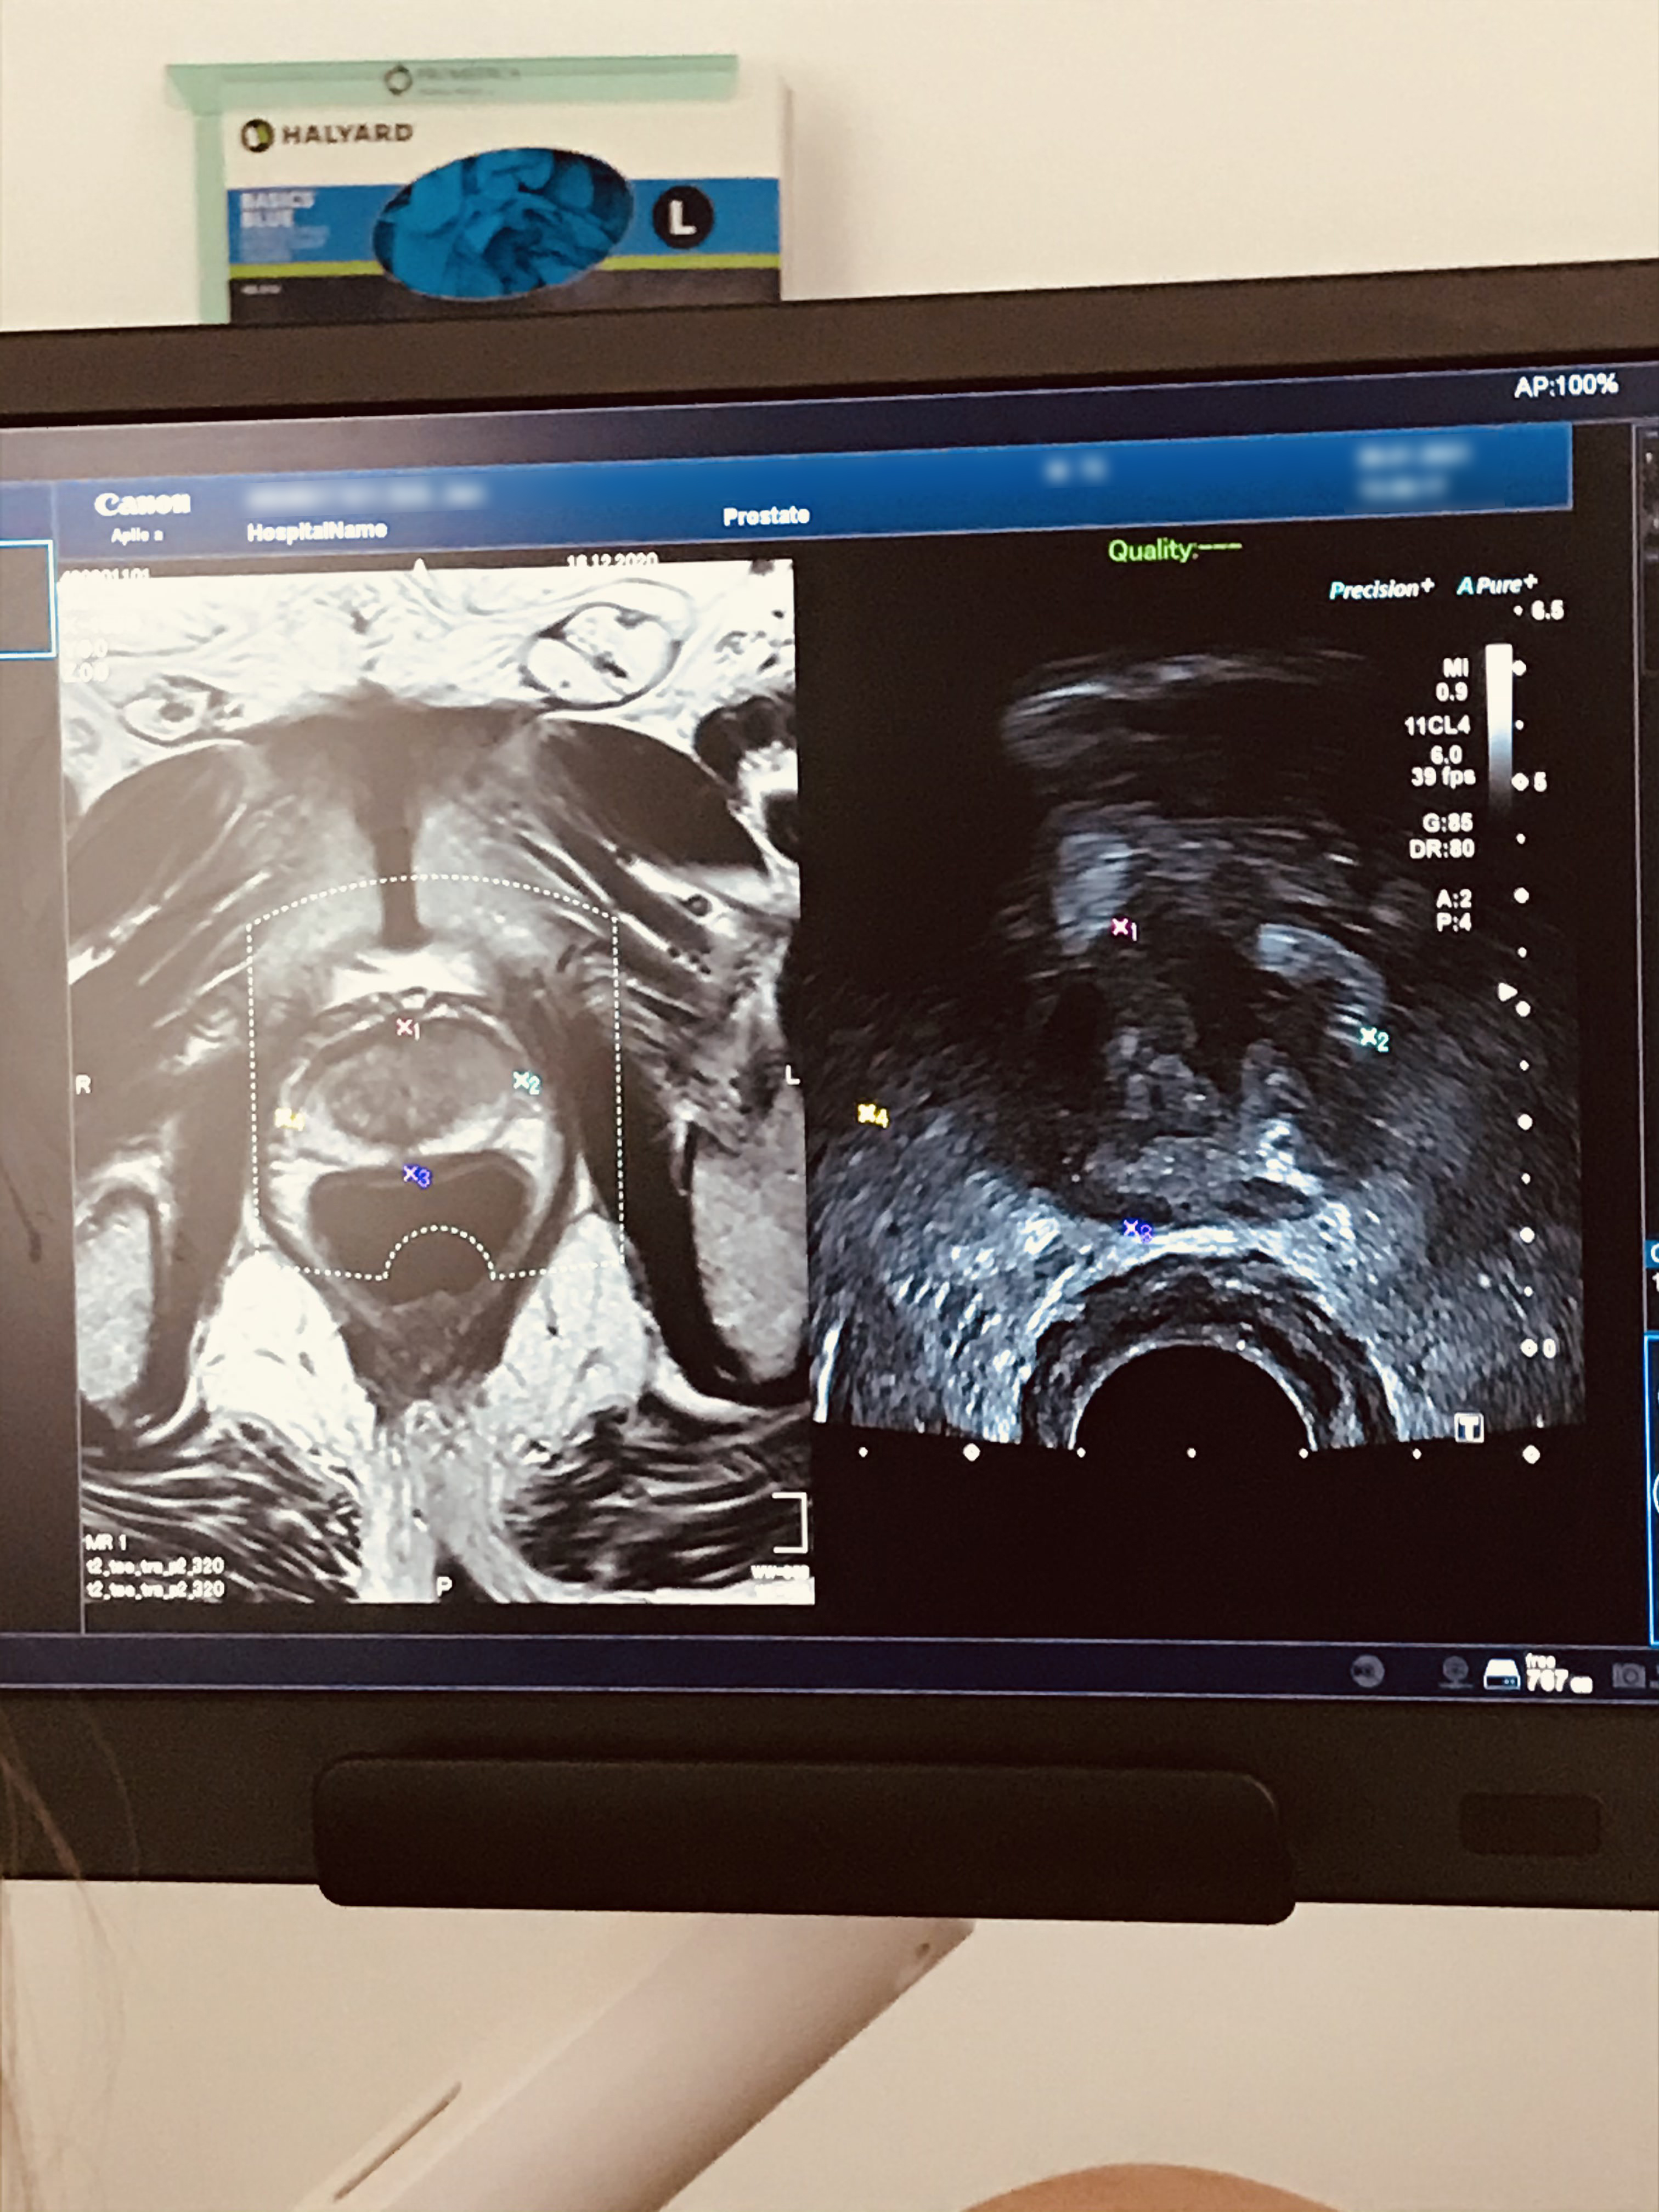

Biopsie prostaty je diagnostické vyšetření, při kterém se pomocí tenké jehly odeberou vzorky tkáně z prostaty. Zákrok probíhá pod kontrolou ultrazvuku, což zajišťuje přesnost. Vzorky se odebírají buď přes stěnu konečníku, nebo přes kůži v oblasti hráze.

V kabince si svléknete boty, kalhoty a spodní prádlo. Samotné vyšetření probíhá na gynekologickém křesle, nebo vleže na boku. Typ přístupu určuje lékař. Během zákroku lékař zavede ultrazvukovou sondu do konečníku, aplikuje látku pro znecitlivění a odebere vzorky tkáně. Celé vyšetření obvykle trvá přibližně 10–15 minut.